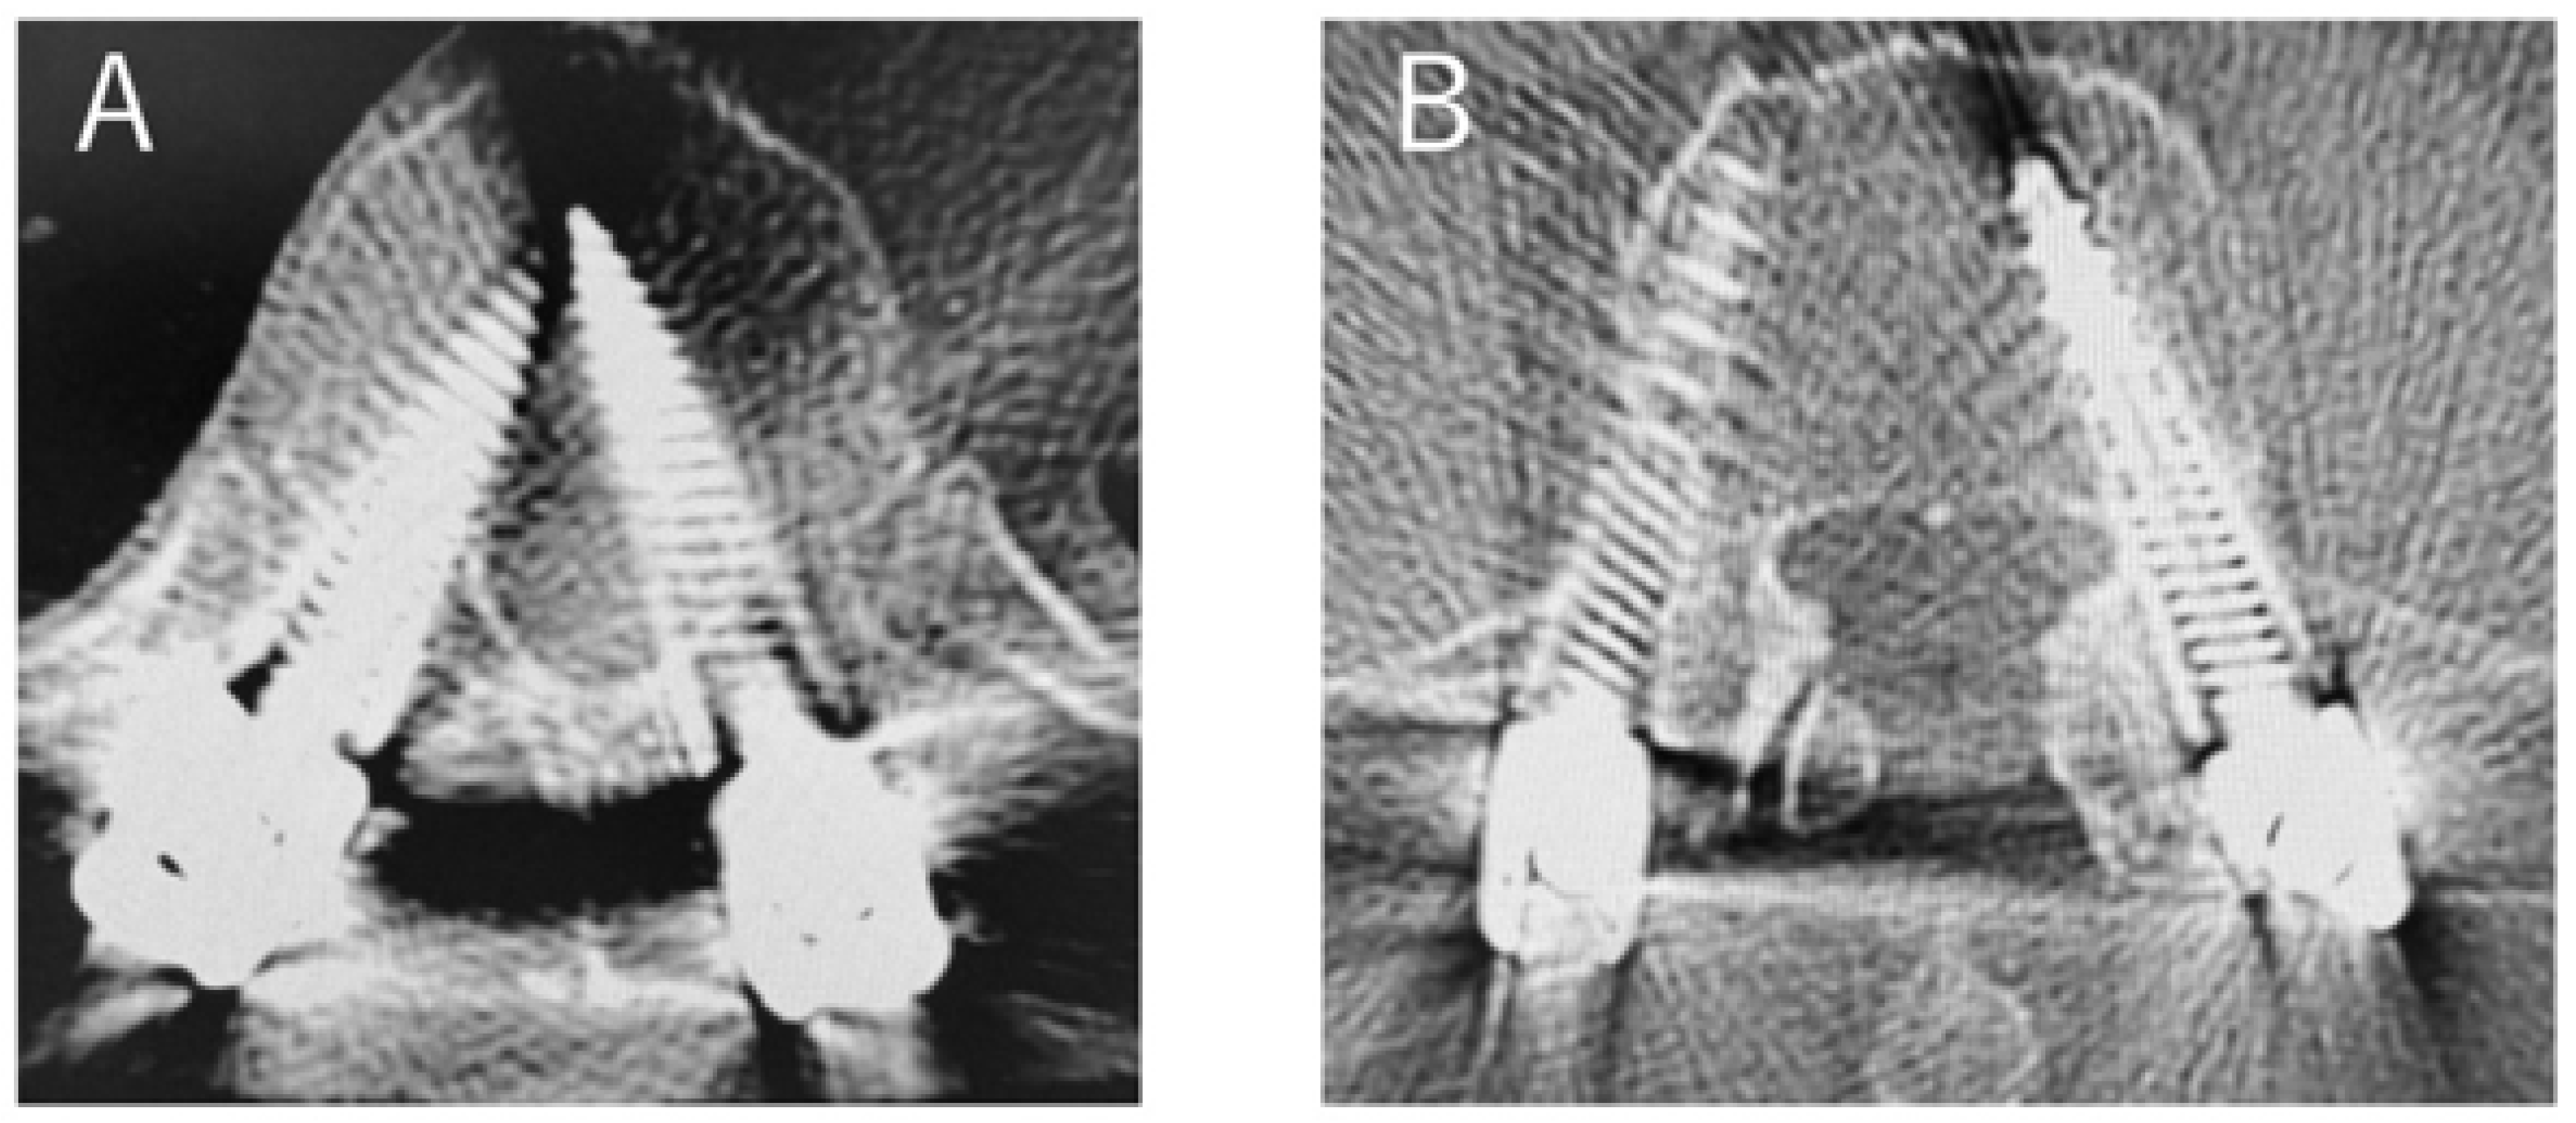

Figure 4.

Case of PPS insertion deviation ((A); 3b with deviation in the insertion of PPSs on the left T11. (B); 1b with deviation in the insertion of PPSs on the right L4).